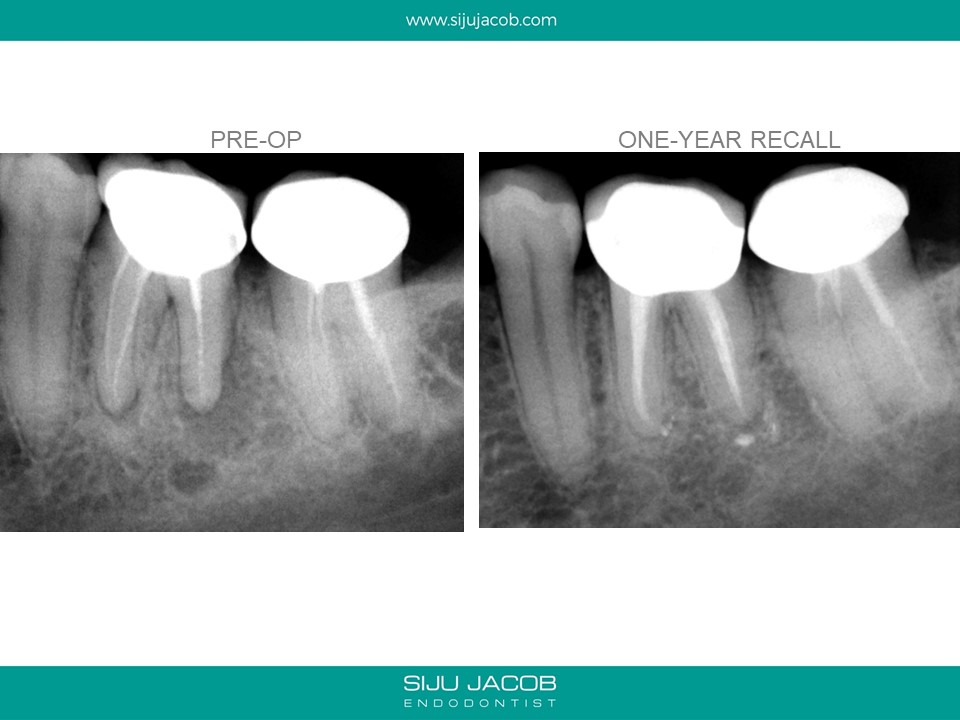

Written by Siju JacobApril 13, 2020 Molar Re-treat with large lesion This patient came with an acute abscess. Disassembly and re-treat with long term Caoh. One year recall shows healing. Share this: Share on X (Opens in new window) X Share on Facebook (Opens in new window) Facebook Like Loading... Related Leave a comment Cancel reply Δ